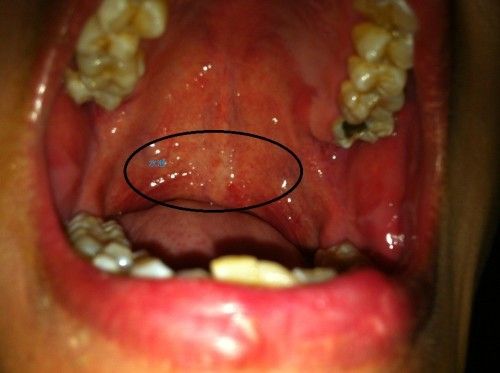

咽炎是指咽部黏膜、黏膜下组织和淋巴组织的炎症,主要分为急性咽炎和慢性咽炎。

- 慢性充血:喉咙黏膜呈暗红色或淡红色,不如急性期那么鲜艳。

- 黏膜肥厚:咽后壁可能因为长期炎症而增厚,看起来不那么光滑。

- 淋巴滤泡显著增生:喉咙后壁上的淋巴滤泡更大、更多,呈颗粒状或鹅卵石样分布,颜色可能是白色或淡红色。

- 咽后壁黏附:常有黏稠的分泌物或“痰”黏在喉咙后壁,难以咳出,是“总觉得有东西”的主要原因。

- 伴随症状:主要为咽干、咽痒、异物感、灼热感、刺激性咳嗽,尤其在晨起时明显。